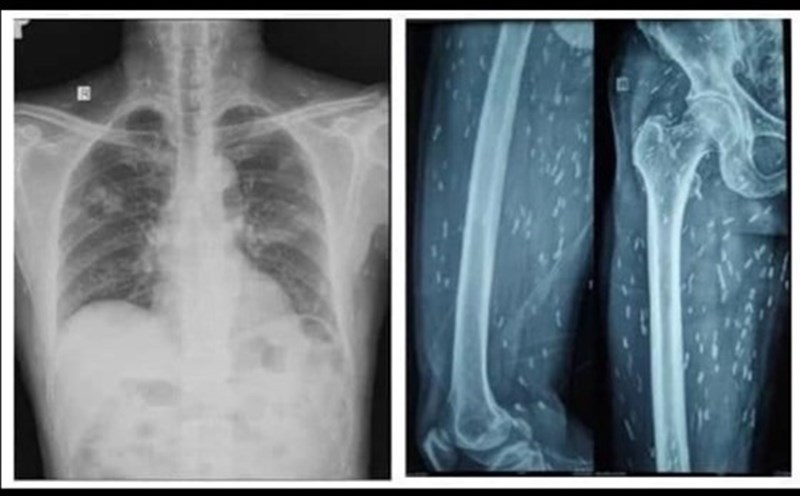

Patient V.G.H (male, 9 years old, Son La) suffered a chest injury, emphysema, fracture of the limb, suspected damage to the pancreas and spleen.

Patient N.D.H (male, 45 years old, Son La) suffered multiple injuries, facial injuries, and open fractures in both limbs.